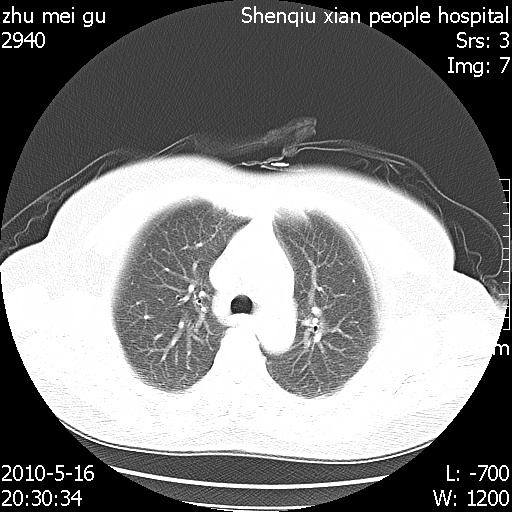

标题: CT26733:能否诊断支扩?

患者,女,62岁,有反复咯血史10年,近三年来大咯血数次,每次量在500-1000ml

图像不全。右中叶内侧段纤维、钙化灶。

没看到支气管扩张的证据

you右肺中叶有点支扩 但不至于咳那么多血啊

图像不全,不像支扩。

不能诊断支气管扩张!

右中叶内侧段慢性感染性病变,不排除合并支气管扩张可能。